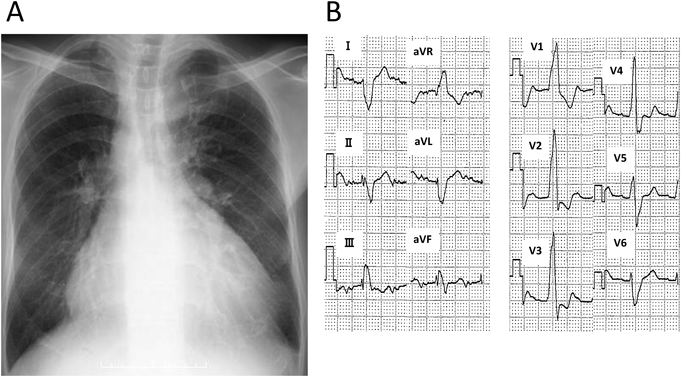

心臓超音波検査

心房逆位で,上下大静脈は左側心房に還流し,心尖下大静脈同側であった.心室正位,左心室は低形成で右心室は高度拡大を認めた.大動脈左前方,肺動脈右後方の転位あり,両大血管右室起始の形態で,心室中隔欠損孔の大きさは径39 mmであった.肺動脈弁と弁上部,および左右肺動脈分岐部に狭窄を認めた.房室弁は共通房室弁であり,弁輪径は54 mmと拡大し,中等度逆流を認めた(Fig. 2).心房中隔は一次孔欠損を認め,径は21 mmで圧較差なく,両心房の拡大を認めた.

Pediatric Cardiology and Cardiac Surgery 33(3): 249-255 (2017)

Fig. 2 Preoperative transthoracic echocardiogram

(A) Color Doppler showing moderate common atrioventricular valve regurgitation. (B) Evidence of valvular and supravalvular pulmonary stenosis.